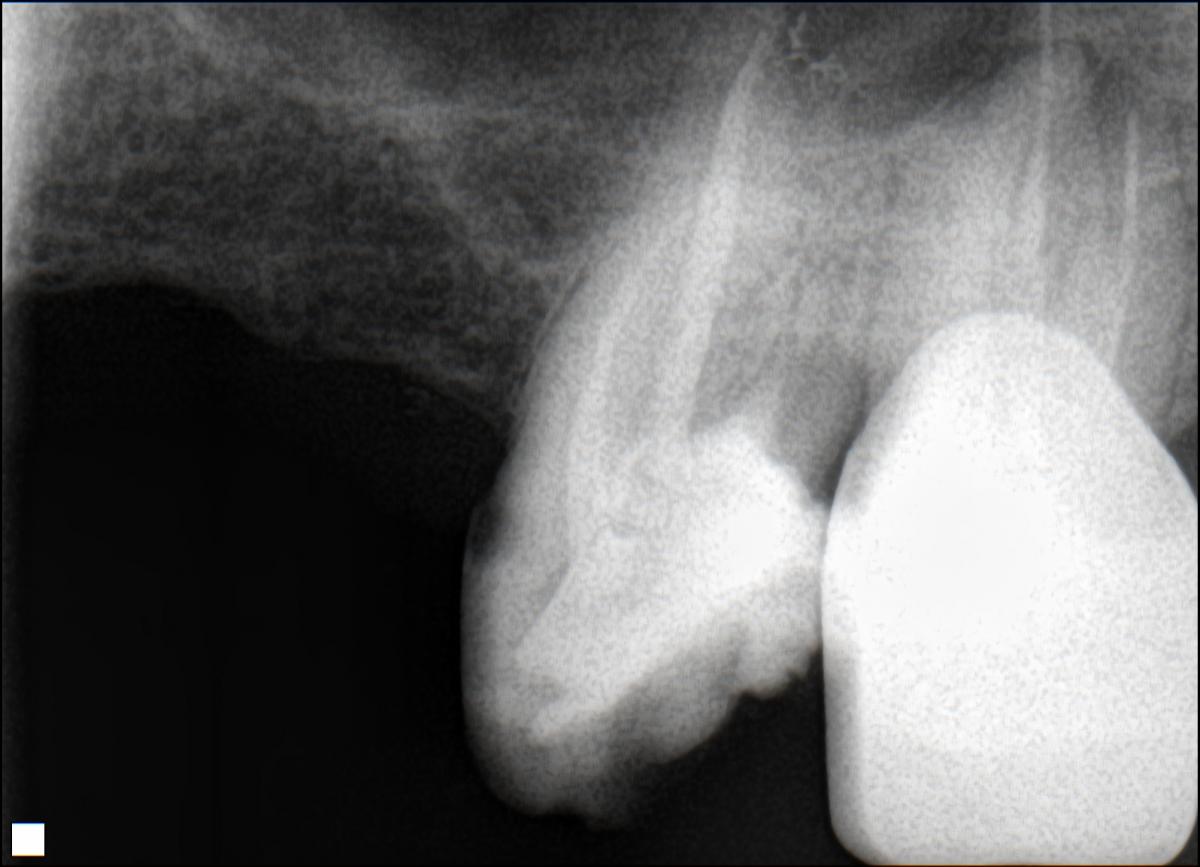

Вот снимок. Видны 2 канала , уже запломбированных

post-58463-0-37531300-1391770327_thumb.jpg

Один только снимок делали? Если честно, мне не понравился этот снимок, но на конечный результат я бы глянул с интересом.

А нужно было сколько сделать снимков? И чем же Вам не понравился снимок? Даст бог, выложу и конечный снимок